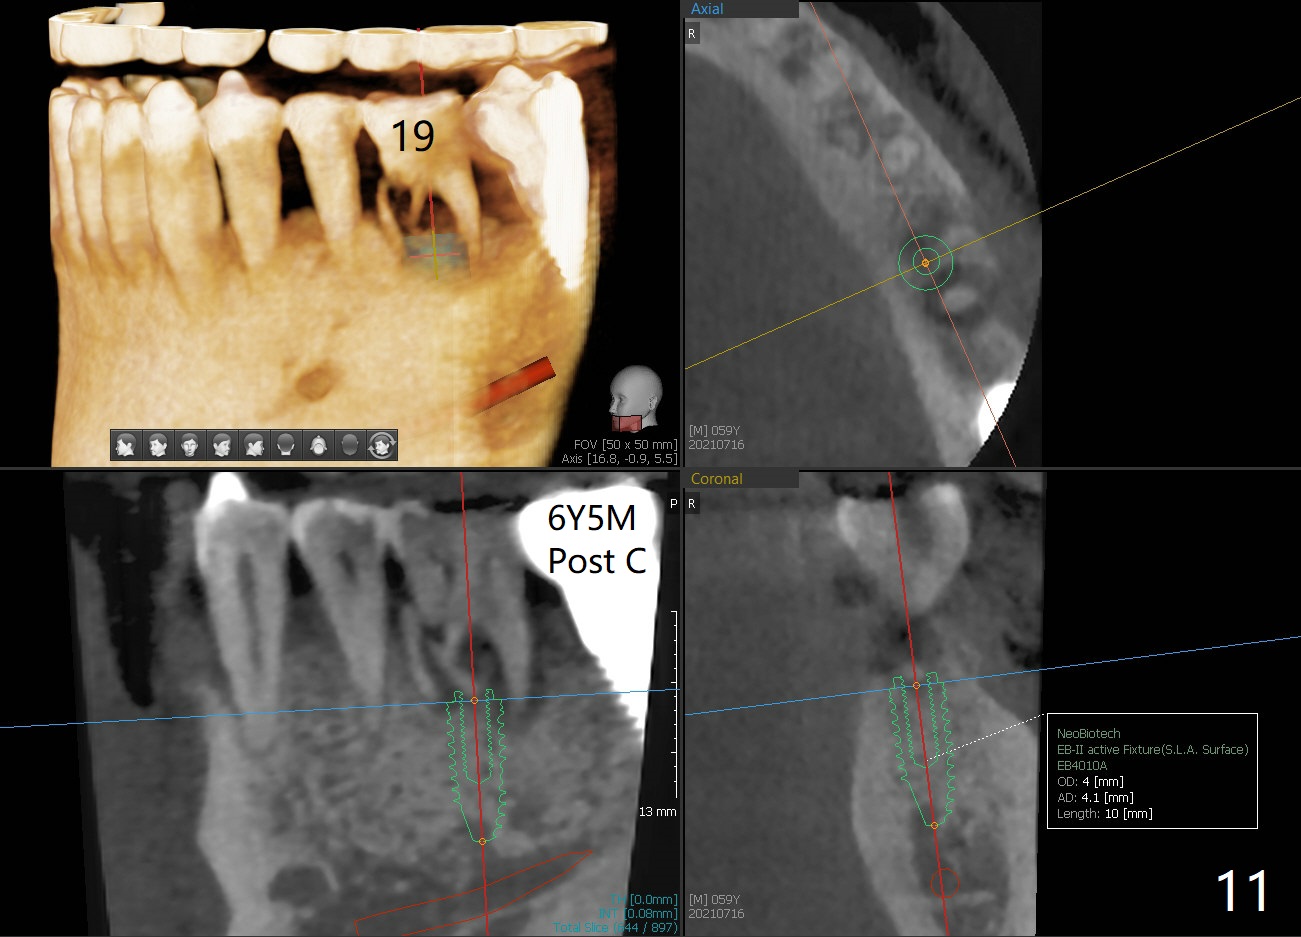

The soft tissue heals around the implant 1 months postop (Fig.1), but the implant (7x11 mm) is unstable. It should have been placed 2 mm deeper (Fig.2). It is splinted for the neighboring tooth (Fig.3). When the splint is removed 4 months later, the implant remains mobile. It is removed with infiltration anesthesia. The osteotomy is deepened by approximately 2 mm. A 7x14 mm tap is inserted with stability (Fig.4); there is apical space to be engaged further (arrowheads). A 7x14 mm implant is placed with insertion torque > 60 Ncm (Fig.5 I); an abutment (A) placed to keep perio dressing in place.

There is no bone resorption 6 months post cementation (12 months postop, Fig.8,9). Mild bone resorption is observed 3 years post cementation (Fig.10). It may be related to the large implant (7 mm) in association with chronic periodontitis and bruxism. The roots of the teeth #19 and 30 fracture 6 years 5 months post cementation at #18 (Fig.11). Since gingival recession is severe at #18 probably related to the large implant, the one at #19 will be designed small.